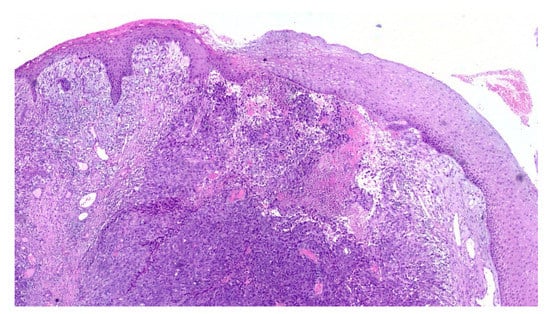

An incisional biopsy of the mass was performed in an area without pigmentation, and the tissue fragment sent for histopathologic examination. Microscopically, the hematoxylin and eosin stained sections revealed a fragment of oral mucosa, lined by keratinized and hypotrophic stratified squamous epithelium (Figure 4), and a dense proliferation of spindle-shaped and epithelioid neoplastic cells in the lamina propria. The tumor cells displayed pleomorphic nuclei with prominent nucleoli and evident mitotic activity (Figure 5). Neoplastic junctional proliferation was detected in some areas.

Figure 4.

Low power view of a poorly demarcated lesion, located in the upper lamina propria (Hematoxylin & Eosin, ×2).